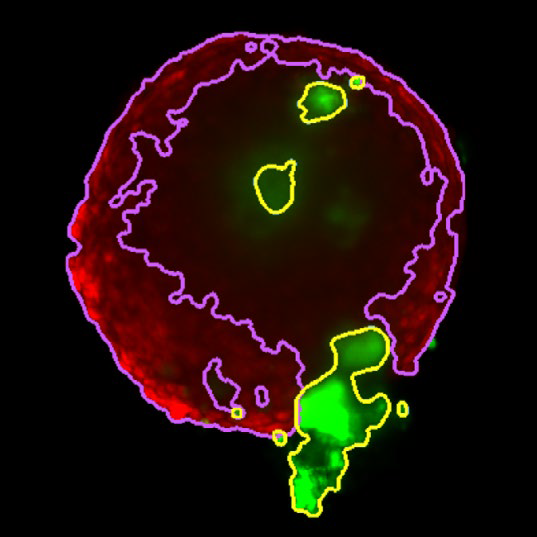

MaxIP image of 3D tumor co-culture microtissue - NCI-N87-GFP (gastric carcinoma; green) and NIH-RFP (murine fibroblast; red)

Figure 2. MaxIP image of 3D tumor co-culture microtissue - NCI-N87-GFP (gastric carcinoma; green) and NIH-RFP (murine fibroblast; red). Image Credit: Yokogawa Life Science

Z slice of the tumor microtissue treated with 0.05% DMSO - tumor (yellow region) and fibroblast (purple region) are recognized separately in 3D

Figure 3. Z slice of the tumor microtissue treated with 0.05 % DMSO - tumor (yellow region) and fibroblast (purple region) are recognized separately in 3D. Image Credit: Yokogawa Life Science

Z slice of the tumor microtissue treated with 5 μM Lapatinib - tumor (yellow region) is decreased significantly comparing to the one treated with 0.005% DMSO

Figure 4. Z slice of the tumor microtissue treated with 5 μM Lapatinib - tumor (yellow region) is decreased significantly compared to the one treated with 0.005 % DMSO. Image Credit: Yokogawa Life Science

Outcome

Tumor spheroids were created by seeding an Akura 384 plate with a monodispersed mixture of GFP-expressing NCI-N87 (gastric carcinoma) and RFP-expressing NIH3T3-L1 (murine fibroblast) cells, which spontaneously formed spheroids through scaffold-free self-assembly over several days. After spheroid formation, selected wells containing tumor spheroids were treated with DMSO at 0.05, 0.5, or 5.0 μM Lapatinib for six days. The images were analyzed in 3D, with NCI-N87-GFP (tumor) and NIH-RFP (fibroblast) identified separately, and the volume of each spheroid measured.